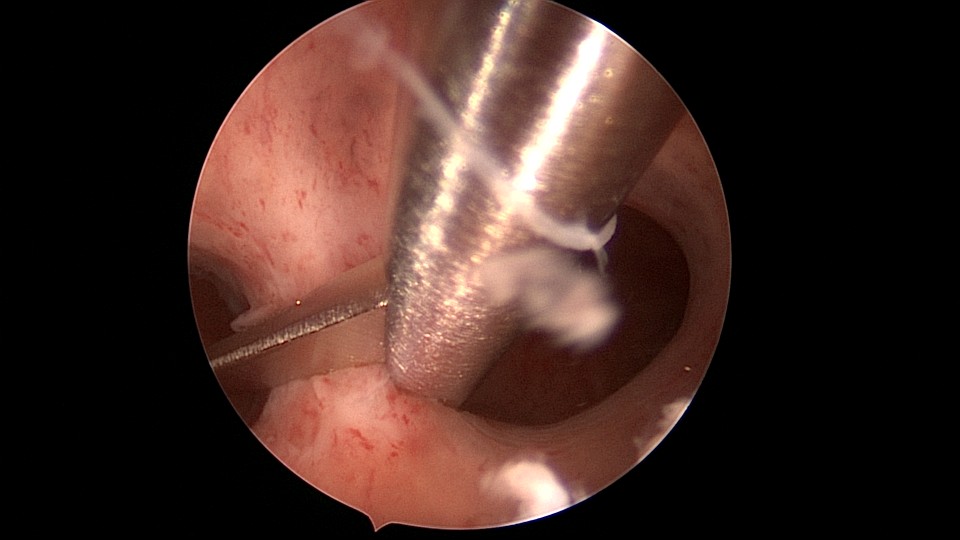

患者29岁,G1P0,继发不孕,2020年8月宫腹腔镜探查,大网膜与腹前壁多处粘连,子宫后壁与直肠前壁广泛粘连,宫腔中央型宽大柱状粘连,宫腔两侧少许粘连。电钩分离盆腔粘连,冷刀分离宫腔粘连,恢复宫腔形态,显露双侧输卵管开口,术中美兰通夜,双侧输卵管通畅。2020年10月宫腔镜二探取球囊,宫腔形态正常,双侧输卵管开口可见。2021年3月自然妊娠,外院足月分娩。现34岁,G2P1。